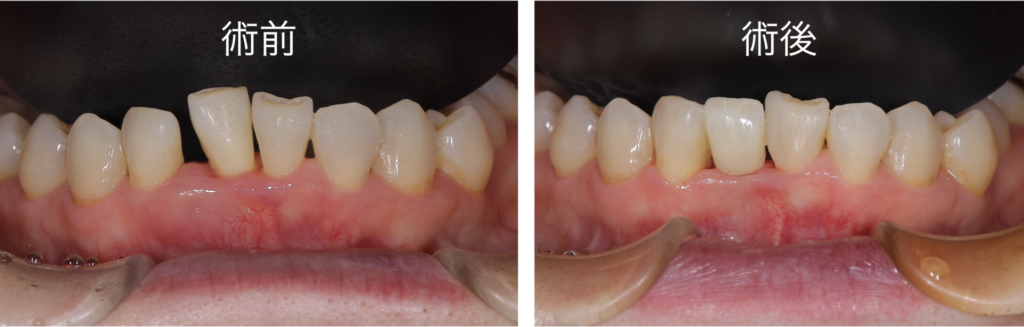

治療の前後の比較写真です

残念ながら抜歯となってしまった歯ですが、隣接する歯を削ることなく審美的に治療を終えることができました

また治療期間につきましても、インプラント治療と比較して大きく短縮することもできました